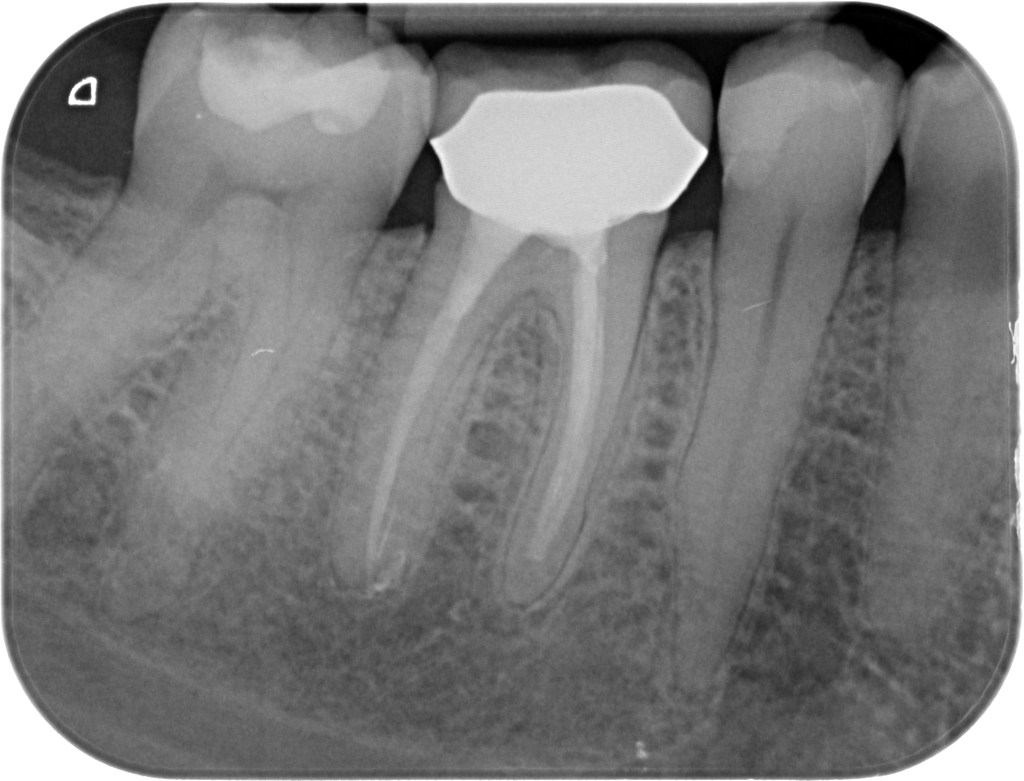

25.03.2021 Patientin DW, geb. am 12.04.1968, Zahn 46,26, WF Revision, WF-Kontrolle minimal 20 Monate post WF